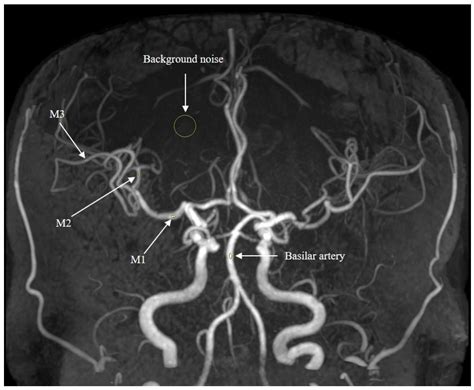

Magnetic Resonance Angiography (MRA) is a specialized application of MRI technology specifically designed to examine blood vessels. While a standard MRI looks at anatomy, an MRA is focused on hemodynamics—the way blood flows through your circulatory system. By manipulating the MRI machine's settings, doctors can highlight blood vessels and create a map of the vascular network.

MRA is primarily used to detect issues such as aneurysms, arterial blockages, narrowing of the vessels (stenosis), or vascular malformations. It is particularly valuable for identifying risks of stroke or heart disease. Because MRA provides a 3D visualization of blood flow, it acts as a critical tool for surgeons and radiologists planning interventional procedures.

Visualization Detailed cross-sectional view of tissue 3D mapping of arterial/venous flow